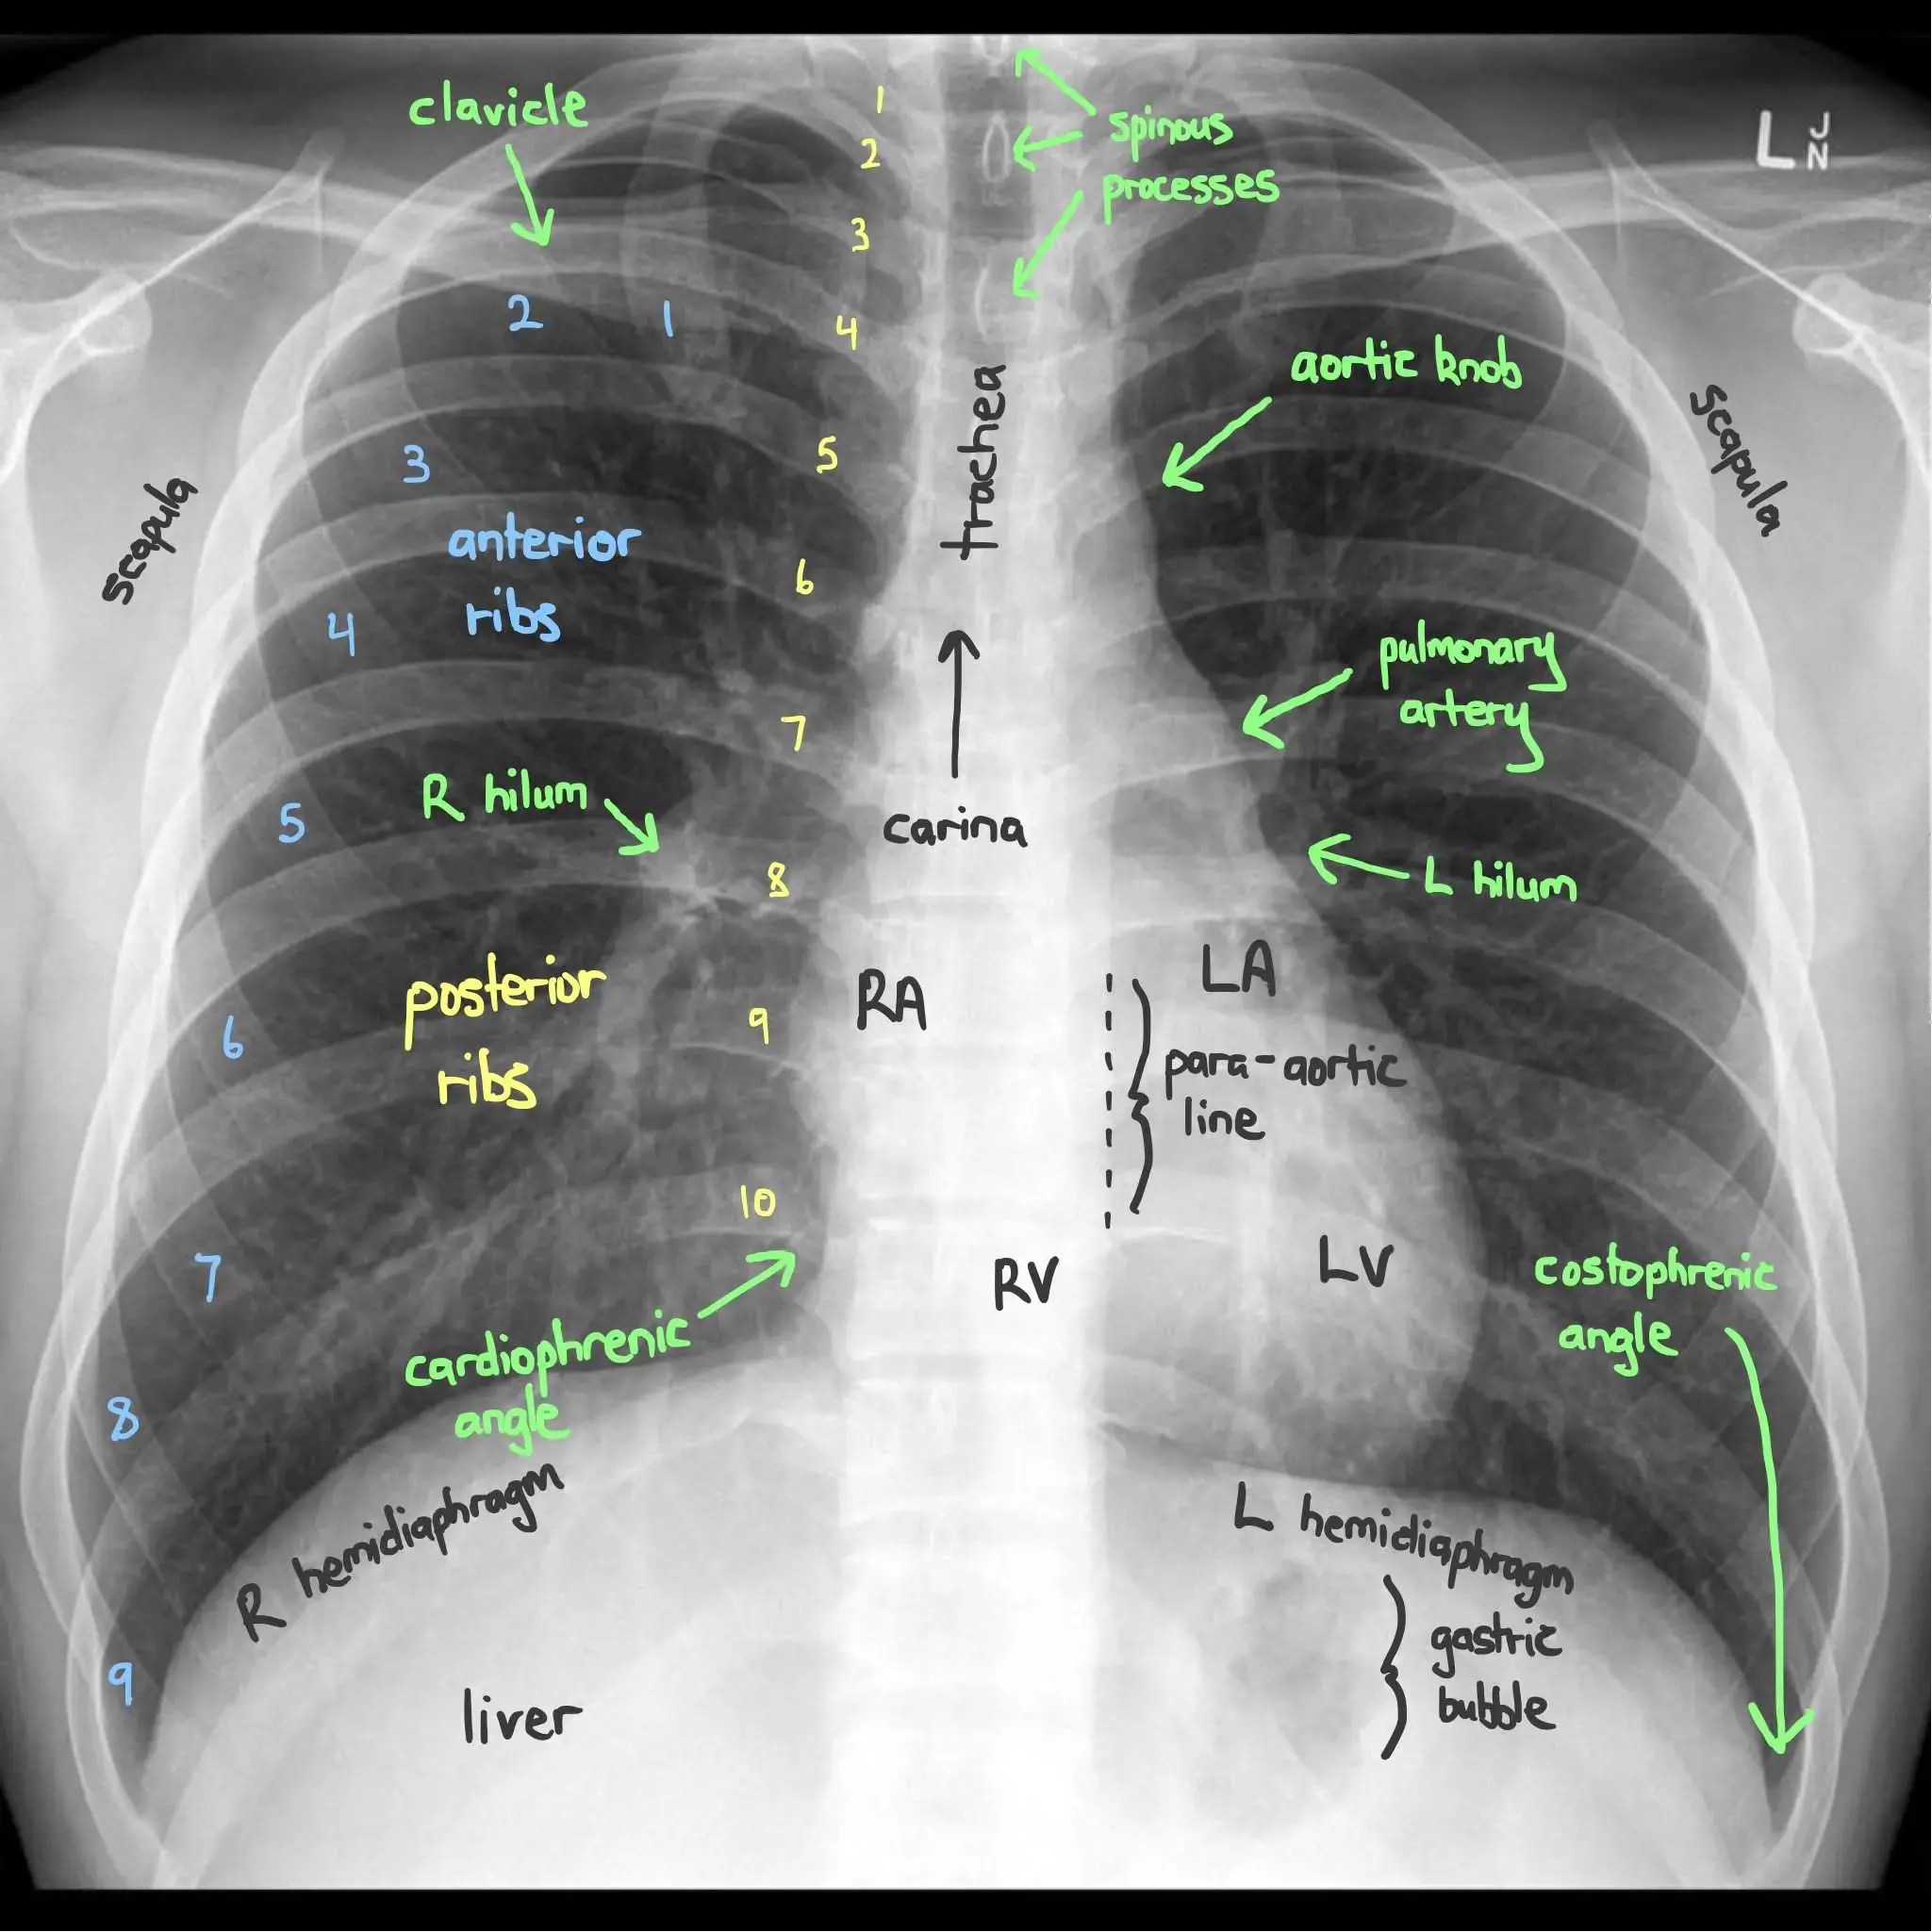

What Does A Normal Cxr Look Like . This image shows a normal chest. It is important to know the normal chest radiograph and common landmarks so that you can recognize what is abnormal. Your ribs, spine, and clavicles should appear intact, aligned, and free. A step by step approach. Darker colors indicate less dense material, and lighter colors indicate more dense material. Use a systematic approach to check the image quality. How to read a normal chest x ray:

Use a systematic approach to check the image quality. This image shows a normal chest. A step by step approach. Your ribs, spine, and clavicles should appear intact, aligned, and free. How to read a normal chest x ray: It is important to know the normal chest radiograph and common landmarks so that you can recognize what is abnormal. Darker colors indicate less dense material, and lighter colors indicate more dense material.